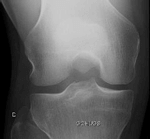

La chondropathie est invisible sur une radio

Sur cette radio de la rotule (Défilé fémoro-patellaire, DFP), le trait jaune montre l'espace (que l'on nomme "interligne"), entre le fémur en bas et la rotule en haut; l'interligne est d'épaisseur normale: il n'y a pas d'arthrose.

La radio ne montre pas les chondropathies sauf au stade de l'arthrose.

Radiographie du genou avec l'incidence fémoro-patellaire (DFP) visualisant l'épaisseur de cartilage entre les deux os (trait jaune)